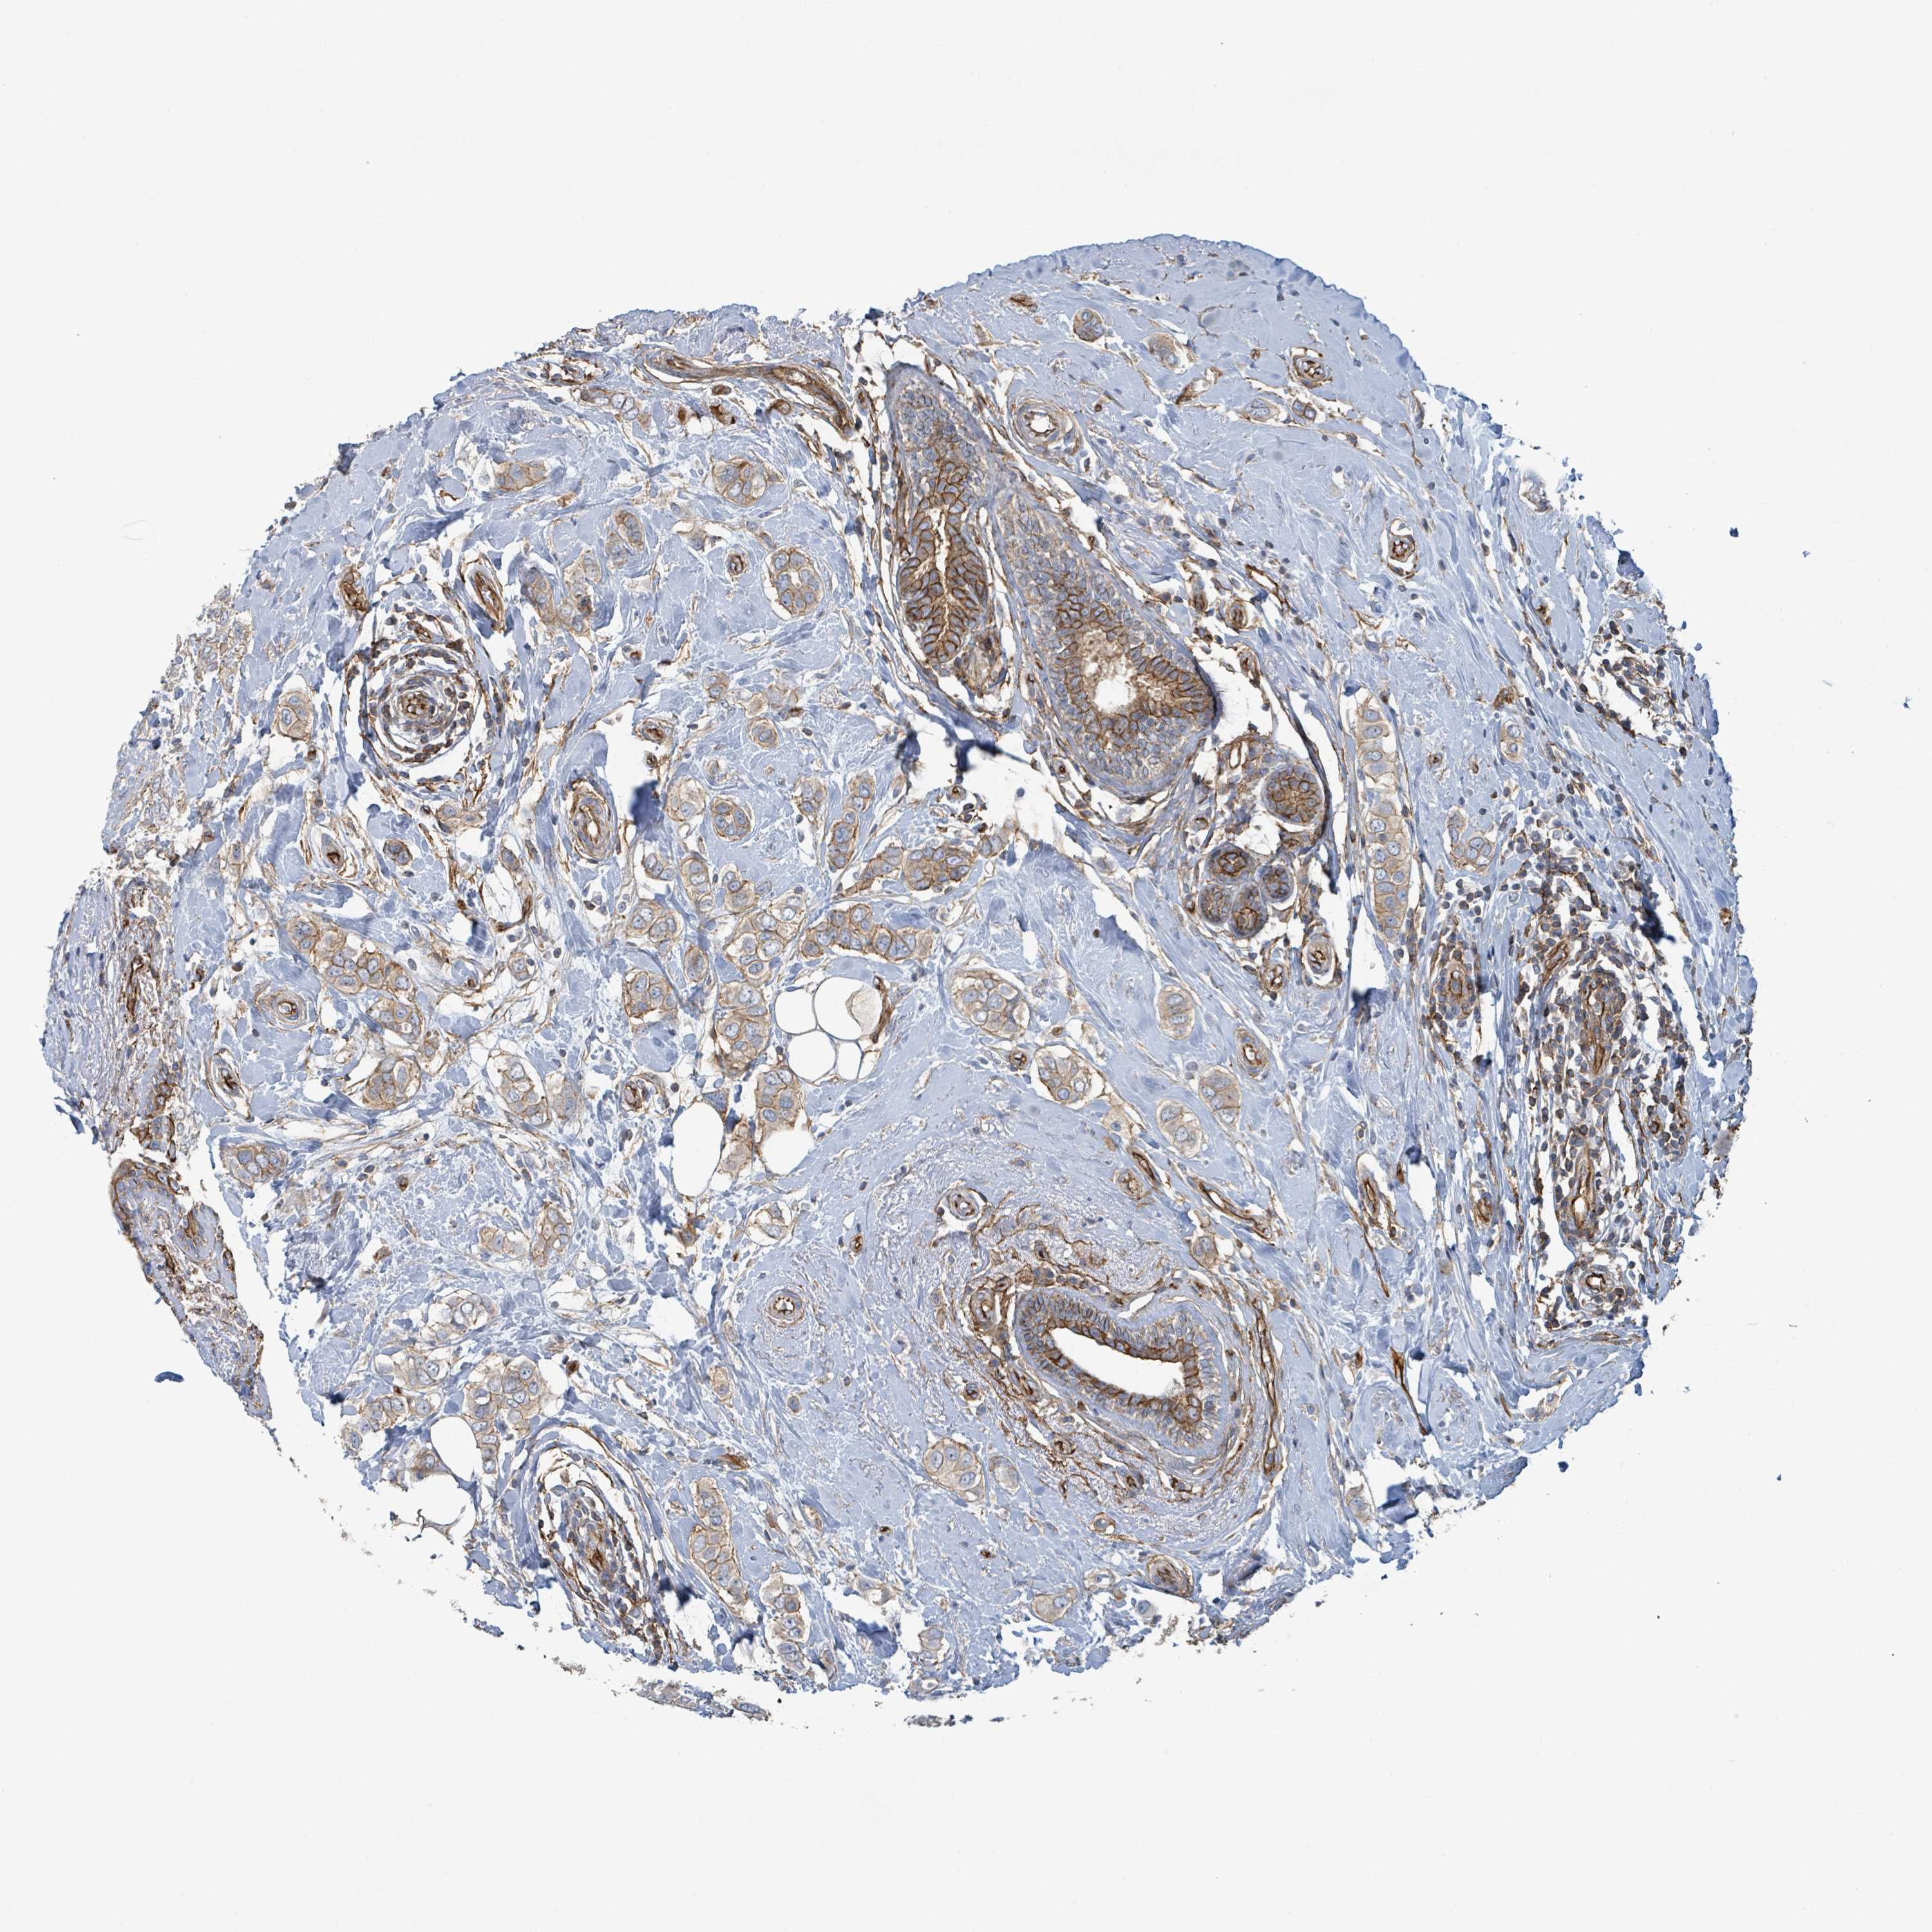

CANCER BREAST CANCER Show tissue menu

BRCA TCGA BRCA VALIDATION PROTEIN EXPRESSION